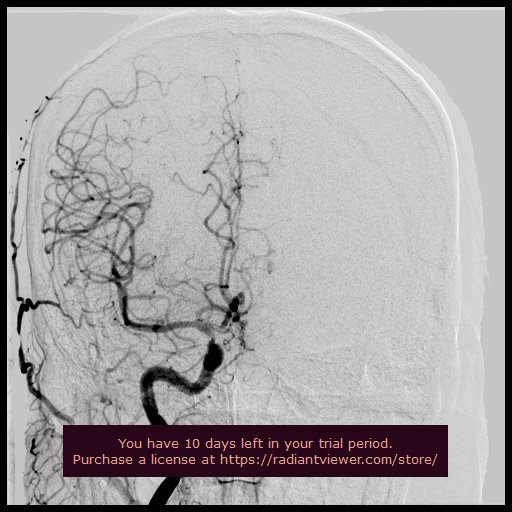

Brain Interventions